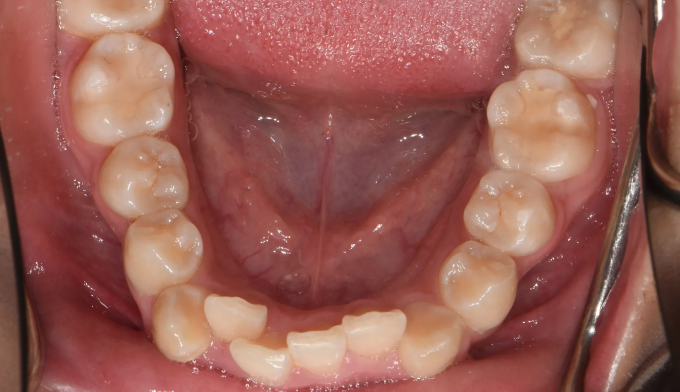

덧니

덧니가 있고, 입도 약간의 돌출감을 보입니다. 발치교정을 통해 이 모두를 해소할 수 있습니다.

치료도중, 환자 본인이 입이 너무 들어가서 얼굴 형태가 급격히 바뀌는것을 걱정하여 입을 최소한으로 집어넣기로 하였습니다. 따라서 발치 공간은 모두 치열을 가지런하는데 이용하기로 하였습니다.

발치후 교정하게 되면 교정을 위한 공간이 충분하므로 입의 전후방 위치를 마음껏 조정할 수 있다는 장점이 있습니다. 교정 중 입술의 모양이나 돌출정도를 바꾸고 싶다면 주치의에게 언제든 말씀해주세요!

교정기간은 20개월 소요되었습니다.